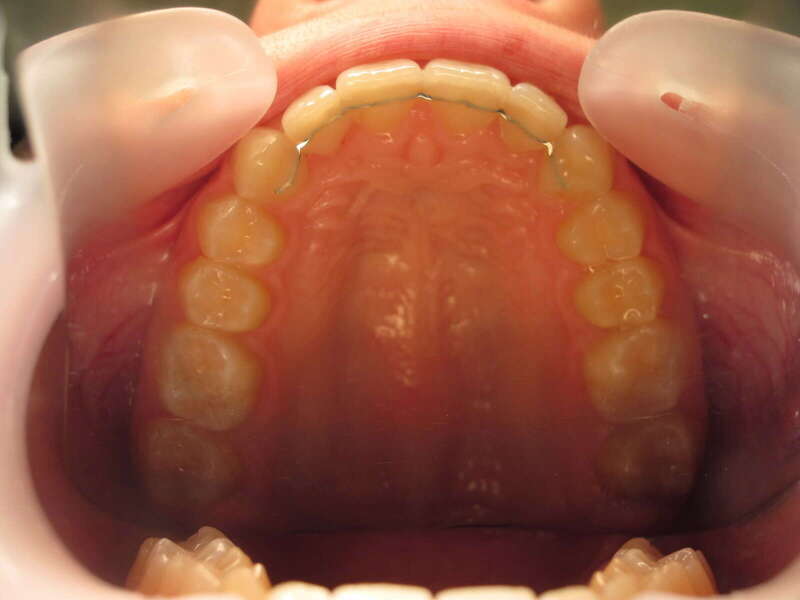

Cas n°1 traité par aligneurs (interception) - enfant

Ce cas d’interception chez un enfant de 8 ans démontre l'efficacité des aligneurs pour corriger des troubles fonctionnels précoces. Le diagnostic présentait des inversions d'articulé provoquant une déviation de la mandibule vers la gauche et un décalage des milieux.

Grâce à une coopération exemplaire et un traitement totalement indolore, l'expansion de l'arcade a permis de recentrer la mâchoire. Cette intervention a littéralement remis la croissance sur les rails, neutralisant le risque d'asymétrie faciale squelettique.

Avant

Après